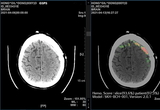

• SK㈜ C&C 'AI 뇌출혈 영상 솔루션 효과' 국제 학술 저널 게재